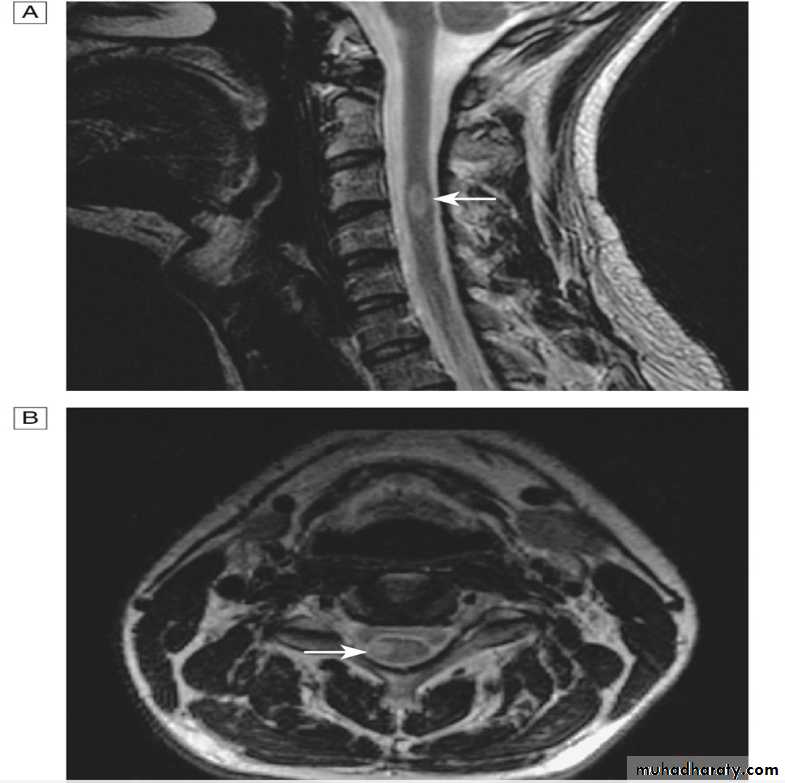

A 42-year-old woman developed progressive bilateral lower extremity numbness and weakness over 5 days, lost the ability to walk, and developed urinary retention. She has also experienced increasingly severe nausea and vomiting over that period. and was found to have an elevated antinuclear antibody during her evaluation for myalgia 3 years ago.Examination shows severe paraparesis, a T9 sensory level, and painful left lower extremity spasms.

A T2-weighted MRI image of her spinal cord shows a lesion extending from T1 to T5 and affecting the central cord. The lesion shows patchy enhancement with gadolinium.

There is increased T2 signal in the area postrema and around the third ventricle.

Neuroimaging characteristics are critical for diagnosis. Identification of an intramedullary cord lesion, especially postgadolinium enhancement, is very helpful in a diagnosis of myelitis

1. MRI of spinal cord with and without contrast (exclude compressive causes).